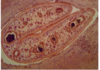

Rumen fluke (histology)